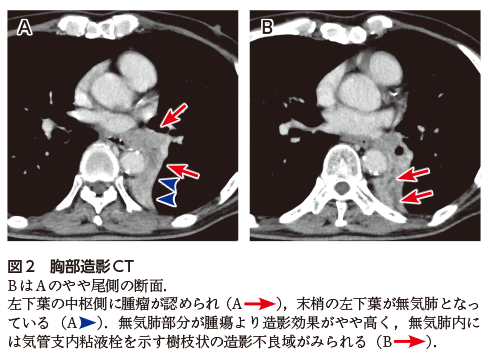

本症例の胸部X線写真では左下肺野縦隔側の心陰影にほぼ重なるように肺野透過性低下がみられ(図1A),この部分で左横隔膜の辺縁が消失し(図1B---),下行大動脈外側縁も不鮮明化している(図1B---).また含気のある左肺野は右肺野と比較し透過性が亢進しており,左上葉の代償性過膨張による変化と考えられる.さらに正常では右側より高い位置にある左肺門が下方に偏位している(図1A).これらの所見から左下葉無気肺と診断可能である.

図1